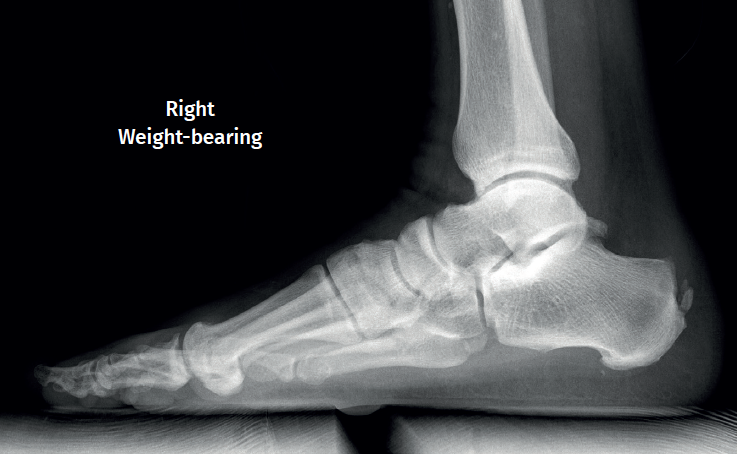

Approximately 6% of the general population will experience some pain episode of the Achilles tendon during life(1). Of these patients, approximately one-third will present tendon insertion damage(2,3). Patients with insertional tendinopathy of the Achilles tendon (ITA) typically experience pain and functional limitation, aggravated by physical activity and following resting periods. They may present thickening of the insertional portion of the tendon, most often at the lateral margin (Figure 1).

Figure 1. Insertional tendinopathy of the Achilles tendon. Thickening of the soft tissues, prominence on the external side.